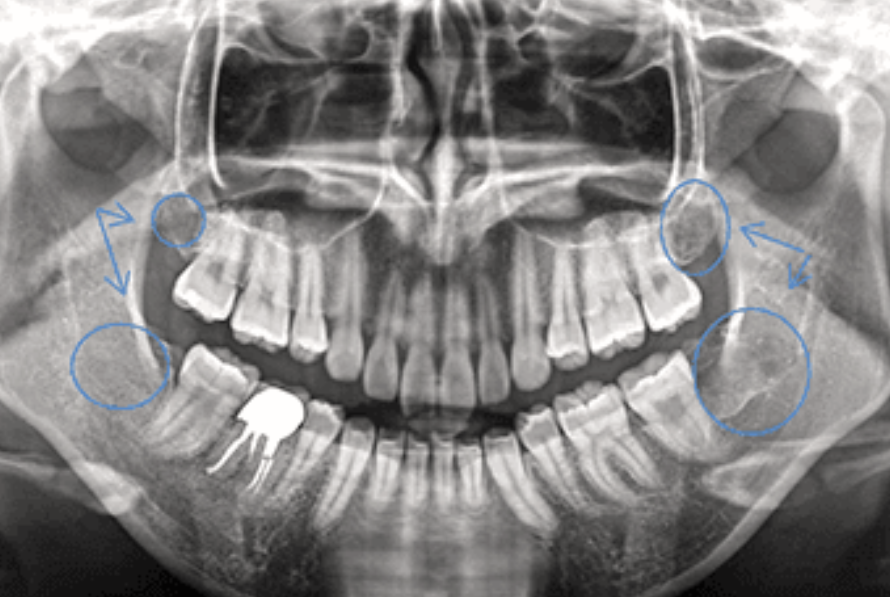

林歯科医院では、口腔外科、特に親知らずの抜歯治療において高度な専門性を発揮しています。埋伏智歯や難抜歯の処置を得意としており、CTを用いて下歯槽管との位置関係を正確に診断し、マイクロルーペやバリオサージなどの専門機器を活用した治療を行っています。

通常の抜歯では困難とされる症例でも、林歯科医院では即日抜歯が可能な場合が多く、最小限の術野で処置を行うことで骨や歯周組織へのダメージを極力抑えることが可能です。そのため、術後の出血、痛み、腫れなどの不快症状を最小限に抑え、早期回復が期待できるのです。

これらの技術力の高さから、他の歯科医院からの紹介も多く受けており、地域の歯科医療における専門性の高さを示しています。抜歯は患者様にとって不安を感じやすい処置ですが、高度な技術と設備により、安心して治療を受けることができる環境が整っています。口腔外科処置の質の高さは、患者様の術後の生活の質にも直結するため、この分野における専門性の高さは歯科医院選びの重要な要素です。